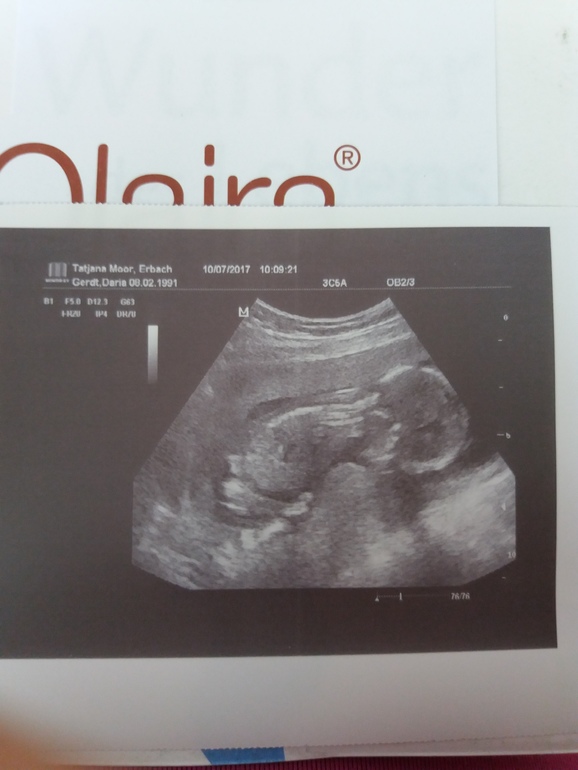

Сегодня 16,3 нед. Ходила сегодня к врачу, с малышом все хорошо,соответствуем сроку 16,6 нед. Пол нам не раскрыли. Ножки не захотел убирать. И вообще решил от нас отвернуться. За 16 недель прибавка +300 гр. Это радует. В первую б была уже около 1,5 кг. В 16,1 нед. почувствовала первый пиночек....такой аккуратненький и нежненький. Уже 2 дня затишье. Малыш прикреплен по задней стенке. На второй скрининг попадаем только на 21 августа в 22 недели. Наша врач уходит в отпуск. Токсикоз начал проходить. Ура. Вот такие у нас новости. Ну и наше фото: